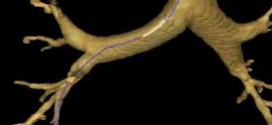

El cáncer de bronquios. Estructura tubular que conduce el aire desde la tráquea a los alveolos pulmonares. Los bronquios son tubos con ramificaciones progresivas arboriformes (25 divisiones en el hombre) y diámetro decreciente, cuya pared está formada por cartílagos y capas muscular, elástica y mucosa. Al disminuir el diámetro pierden los cartílagos, adelgazando las capas muscular y elástica. La Función …